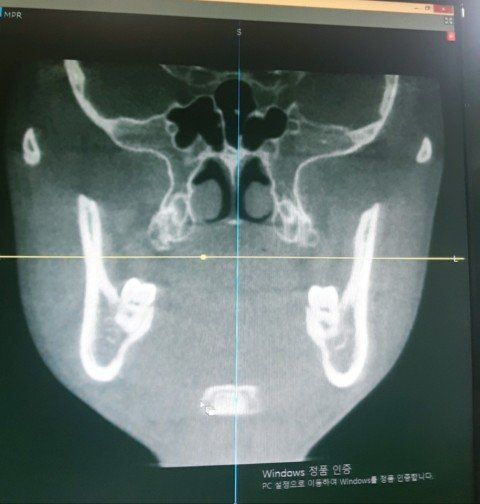

입안 잇몸밑에 하악쪽 뼈있는곳이 자까 벗겨지고 까지집니다. 2년넘게 증상이 나아지지 않고 혀로 문질러 보면 느낌도 까칠하고 무슨 지렁이 같은게 붙어 있는거마냥 그런 느낌이 납니다 손가락으로 긁어서 보면 지우개 가루같이 흰색으로 되어있는 이물질들이 나옵니다. 치과에 가보니 충치 치주질환 등 그런것들은 아니라고 (인천에 있는 대학병원)큰병원에 가보라고 해서 혹시나 악성이 아닐까 걱정도 하고 ct도 찍어보았으나 아무런 문제가 없다고 하는데... 증상은 계속돼고... 이유가 뭘까요? 참고로 제가 후두염 식도염 있고 그리고 위가 좀 안좋은것같은데 연관성이 있을까요?

(인천에 위치한)대학병원에서 촬영한 것입니다.